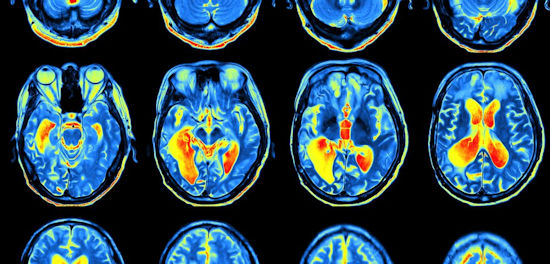

La muerte celular inducida por hierro puede contribuir a la progresión de la ataxia de Friedreich, según muestra un estudio en células humanas y de ratones... La inhibición de este mecanismo degenerativo puede representar una nueva estrategia terapéutica para los afectados por esta rara enfermedad, sugieren los investigadores.

Algunas de las principales características celulares y moleculares de la ataxia de Friedreich, en particular la acumulación de hierro mitocondrial, el aumento del estrés oxidativo, y la peroxidación lipídica, también son características distintivas de una vía de muerte celular, llamada ferroptosis.

La ferroptosis se describió por primera vez en el año 2012, y se ha relacionado con la degeneración de células nerviosas en las enfermedades de Parkinson y Alzheimer. Ahora, un equipo dirigido por investigadores del Hospital de Niños de Filadelfia ha explorado el papel de la ferroptosis en la ataxia de Friedreich.